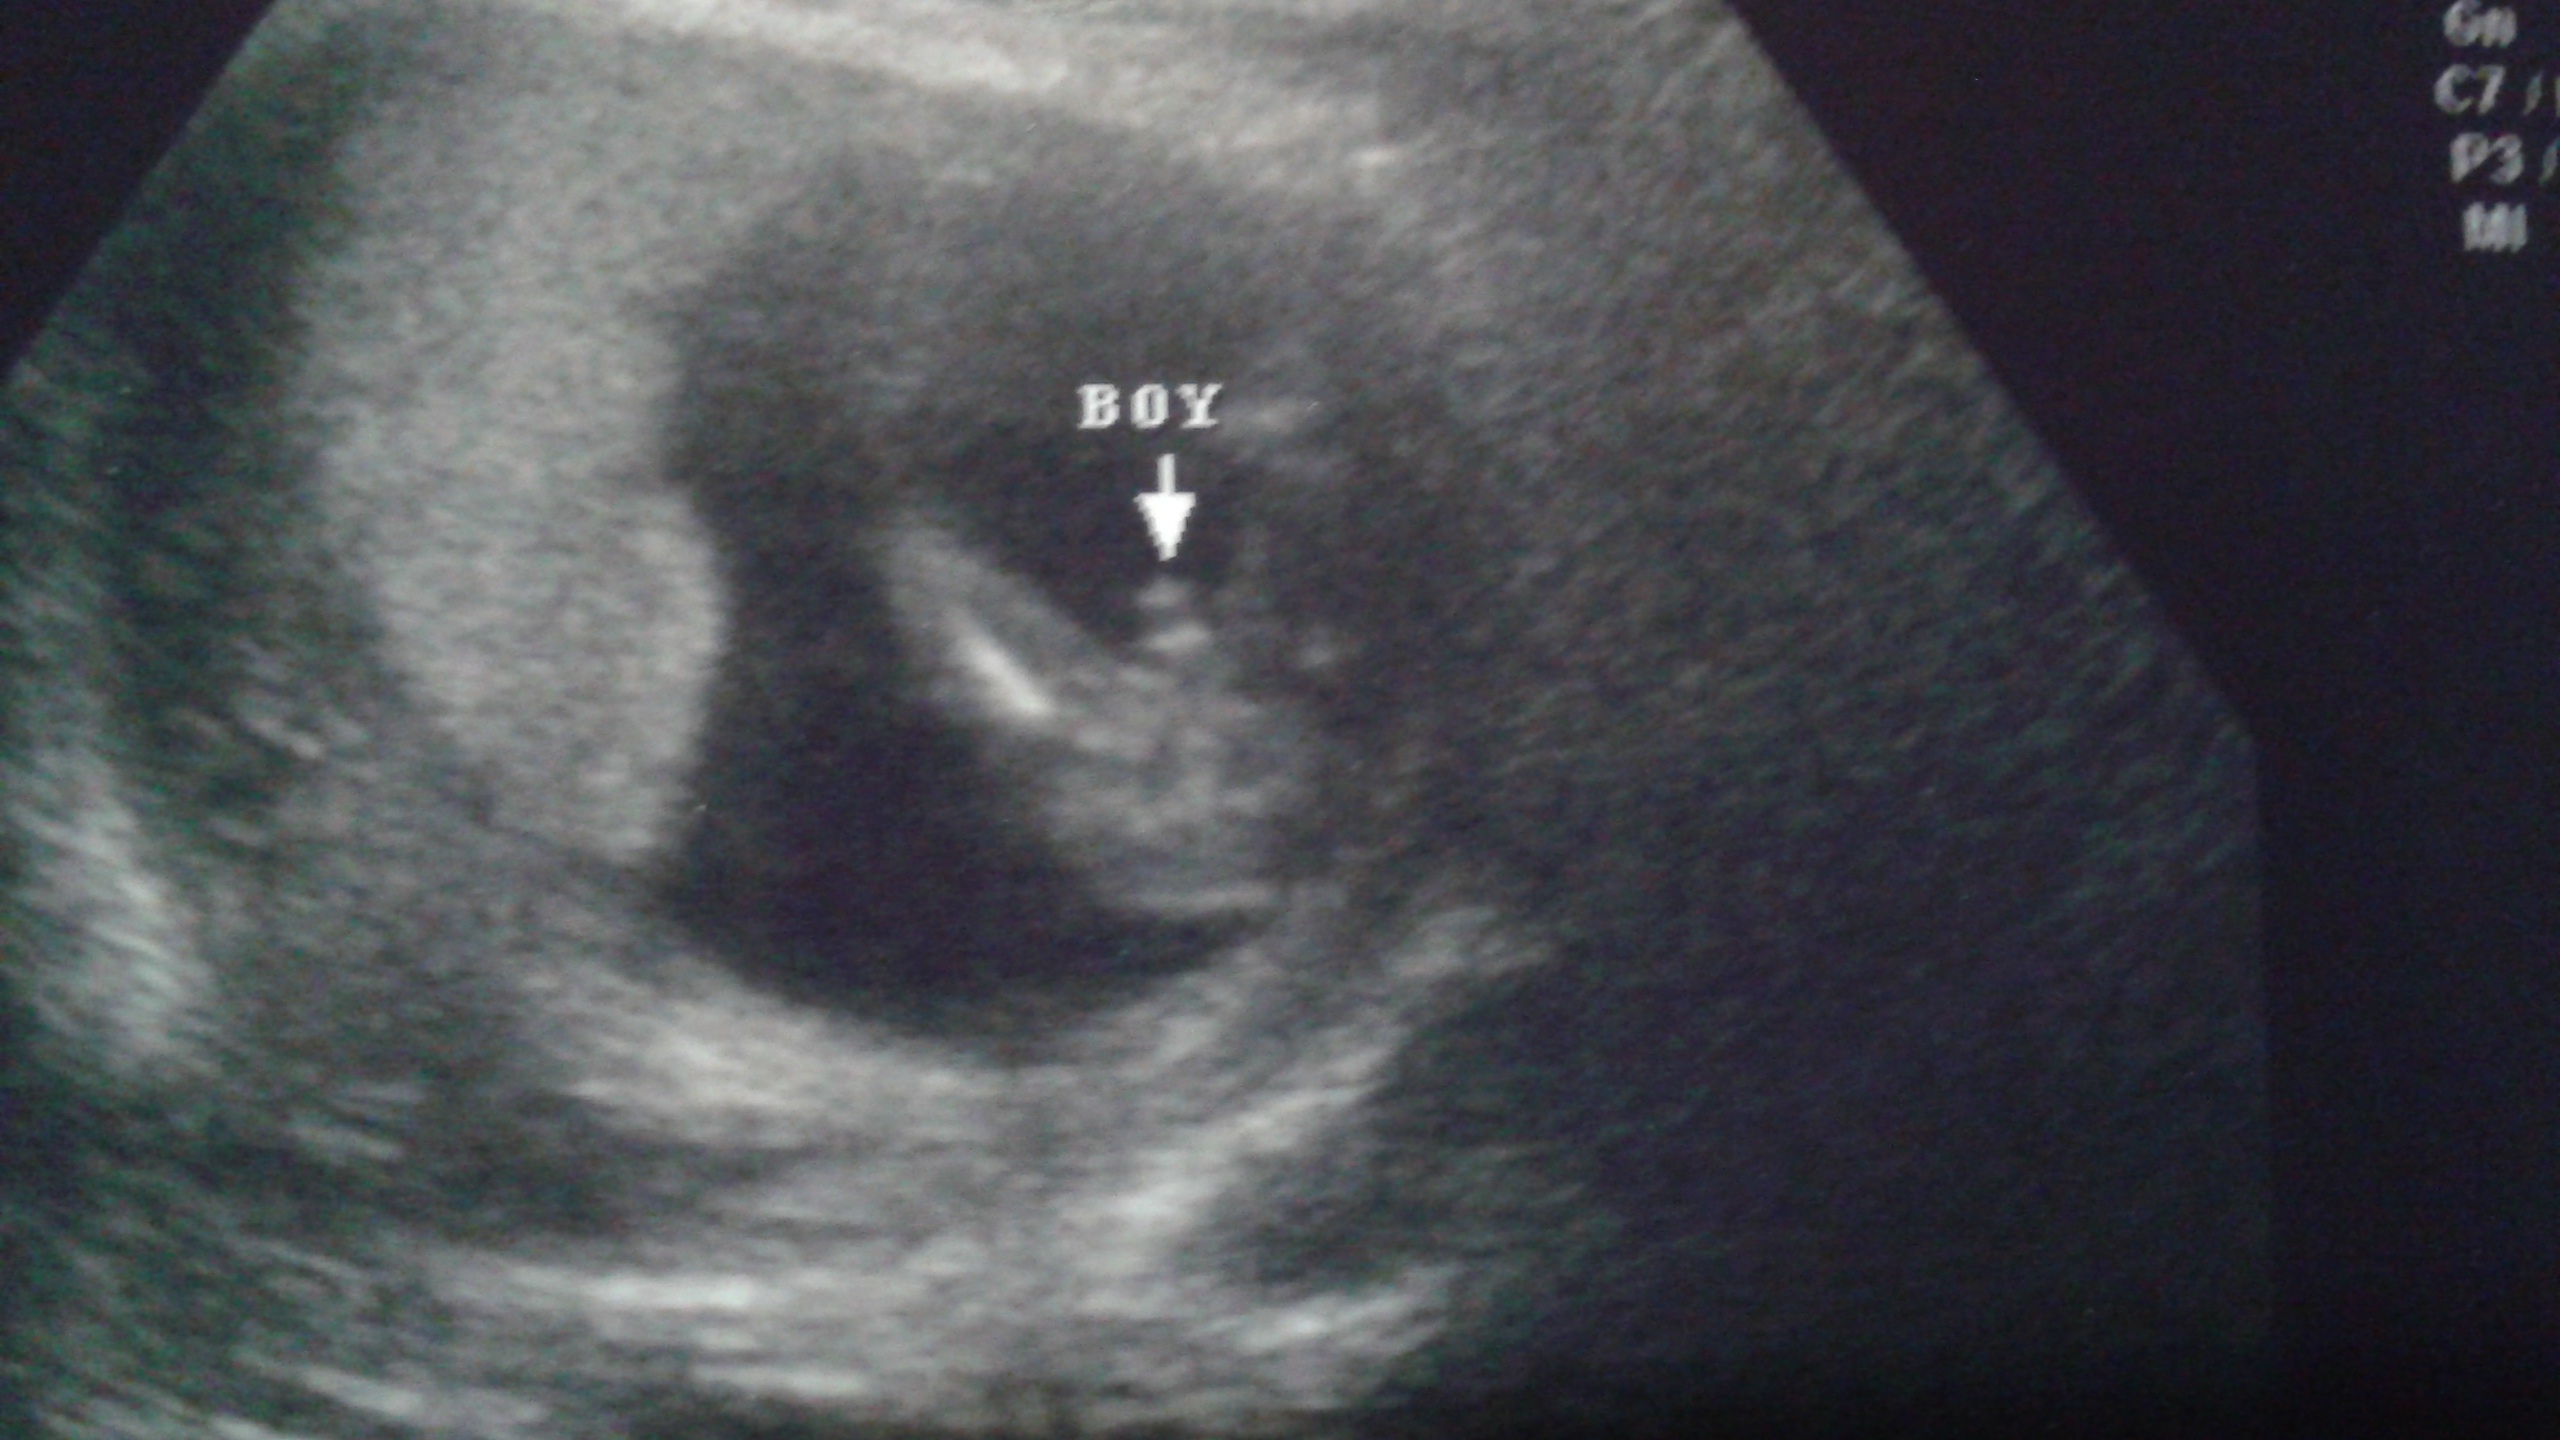

• It all depends. I had one done and i pay $39 to determine baby sex.. We are having a boy. We have 2 girls already.Im 15 weeks and clearly it showed boy parts. Baby was showing it off during the whole 15 mins on ultrasound we even got a dvd of the whole 15 min section with lullaby. So it was worth it for us.

image